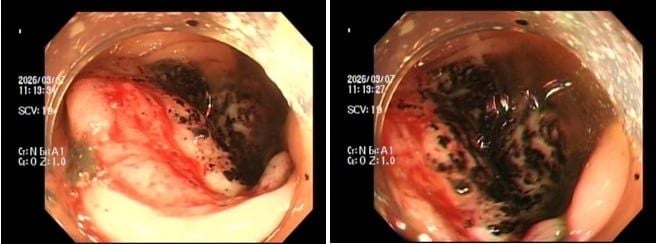

Trường hợp 1, chị P.V.P.U (sinh năm 1991) đến khám chỉ vì... ông xã thấy dạo này da dẻ chị quá xanh xao. Bản thân chị thỉnh thoảng cũng cảm thấy đôi lúc đau bụng nhẹ, nhưng lại tặc lưỡi bỏ qua vì nghĩ là rối loạn tiêu hóa thông thường. Khi thăm khám, bác sĩ phát hiện chị bị thiếu máu nặng. Ngay lập tức, chị được chỉ định nội soi đại tràng, kết quả khiến cả hai vợ chồng sững sờ: Có một khối u lớn ở đại tràng phải, bề mặt loét và rất dễ chảy máu, kết quả mô học khẳng định: Ung thư đại trực tràng.

Trường hợp 2, anh N.H.H.H (sinh năm 1995) đến viện với dáng vẻ mệt mỏi rã rời, than phiền hay bị chóng mặt kèm theo rối loạn đi cầu. Cứ nghĩ do làm việc quá sức, nhưng kết quả xét nghiệm lại báo động tình trạng thiếu máu nặng. Bác sĩ cho tiến hành nội soi đại trực tràng và phát hiện một khối u dạng vòng nhẫn đang chảy máu rỉ rả ở vùng trực tràng. Giải phẫu bệnh một lần nữa gọi tên: Ung thư trực tràng.